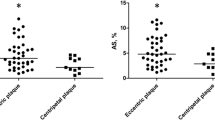

Relation between tissue characterization and mechanical properties on regional analyses

The plaque area, and the parameters derived from the IB-IVUS and ST-IVUS of every ROI are shown in Table 4. Average plaque areas of the inner-clockwise, the inner-counter, the lateral-clockwise, and the lateral-counter were 1.15 ± 0.35 mm2, 1.13 ± 0.33 mm2, 0.91 ± 0.29 mm2, and 0.92 ± 0.31 mm2, respectively. The plaque areas near the area of plaque maximum thickness (the inner-clockwise and the inner-counter) were larger than those of the ROIs far from the area of plaque maximum thickness (the lateral-clockwise and the lateral-counter). In the EEM strain, a significant difference was observed in post hoc test after ANOVA for the lateral-counter site (2.60 ± 2.08%) and the inner-clockwise site (1.93 ± 1.66%). However, there were no significant differences in the tissue characteristics and the mechanical properties among the other ROIs. Relations between the tissue characteristics derived from IB-IVUS and the strains derived from ST-IVUS are shown in Table 5. In the entire ROIs, there were significant associations between the EEM strain and the plaque area of the ROI, and between the LA strain and the %CA (Table 5 and Fig. 5). Regarding the relationship among the main plaque components (the %FI, the %LP) and the strain, significant relationships were found only between the EEM strain and the %FI and between the EEM strain and the %LP at the inner-clockwise site.

In this study, we evaluated the relations between the tissue characteristics derived from IB-IVUS and the strains derived from ST-IVUS. The principal findings are as follows: in the global cross-sectional area analyses, the tissue characteristics of coronary plaques (the %FI and the %LP) had no associated strains; a significant (albeit weak) correlation was observed between %CA and the strain. And even performing regional analyses, the relationship among the strain and the main components (the %FI and the %LP) were weakly associated in a partial set of the ROIs.

Similarly, in a previous study using virtual histology IVUS (VH-IVUS) and palpography, a significant inverse relationship was observed between relative calcium area and strain level [15]. We expected to find a low strain value in a hard component such as calcification. Furthermore, in the present study, the main coronary tissue characteristics (lipid pool, fibrous component) were not associated with strains. This result also corresponded to a previous study where the relations among strains derived from palpography and tissue characteristics derived from VH-IVUS were not significant (strains vs. %fibrosis; r = 0.06, p = 0.55, strains vs. %fibrolipidemic r = − 0.13, p = 0.15) [15]. This trend was also observed in the Rotterdam classification score categorized by maximum strain value [16]. In a carotid artery study, which compared strain derived carotid artery ultrasonography to histology from carotid endarterectomy, no significant correlation was found between strain parameters and cap thickness, smooth muscle cell concentration, or macrophage concentration [21]. The study pointed out that strain is not a direct result of the presence of one histological component, but a representation of the interaction among all components. Our findings support that in clinical practice, strain does not directly reflect the presence of a single plaque component in coronary plaques.